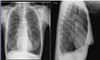

2) Beskriv væsentligste fund på vedlagte røntgenbillede af thorax.

- Emfysematisk thoraxform

- Ingen infiltrater

- Let sløring af sinus phrenicocostalis bilat

- Normal hjertekarstamme

(Max 5 points - 1 point for hvert delelement. Hvis alle ting er nævnt, gives 1 point ekstra)

2. Skulle du beskrive et røntgen thorax, hvor svaret er

- Emfysematisk thoraxform

- Ingen infiltrater

- Let sløring af sinus phrenicocostalis bilat

- Normal hjertekarstamme